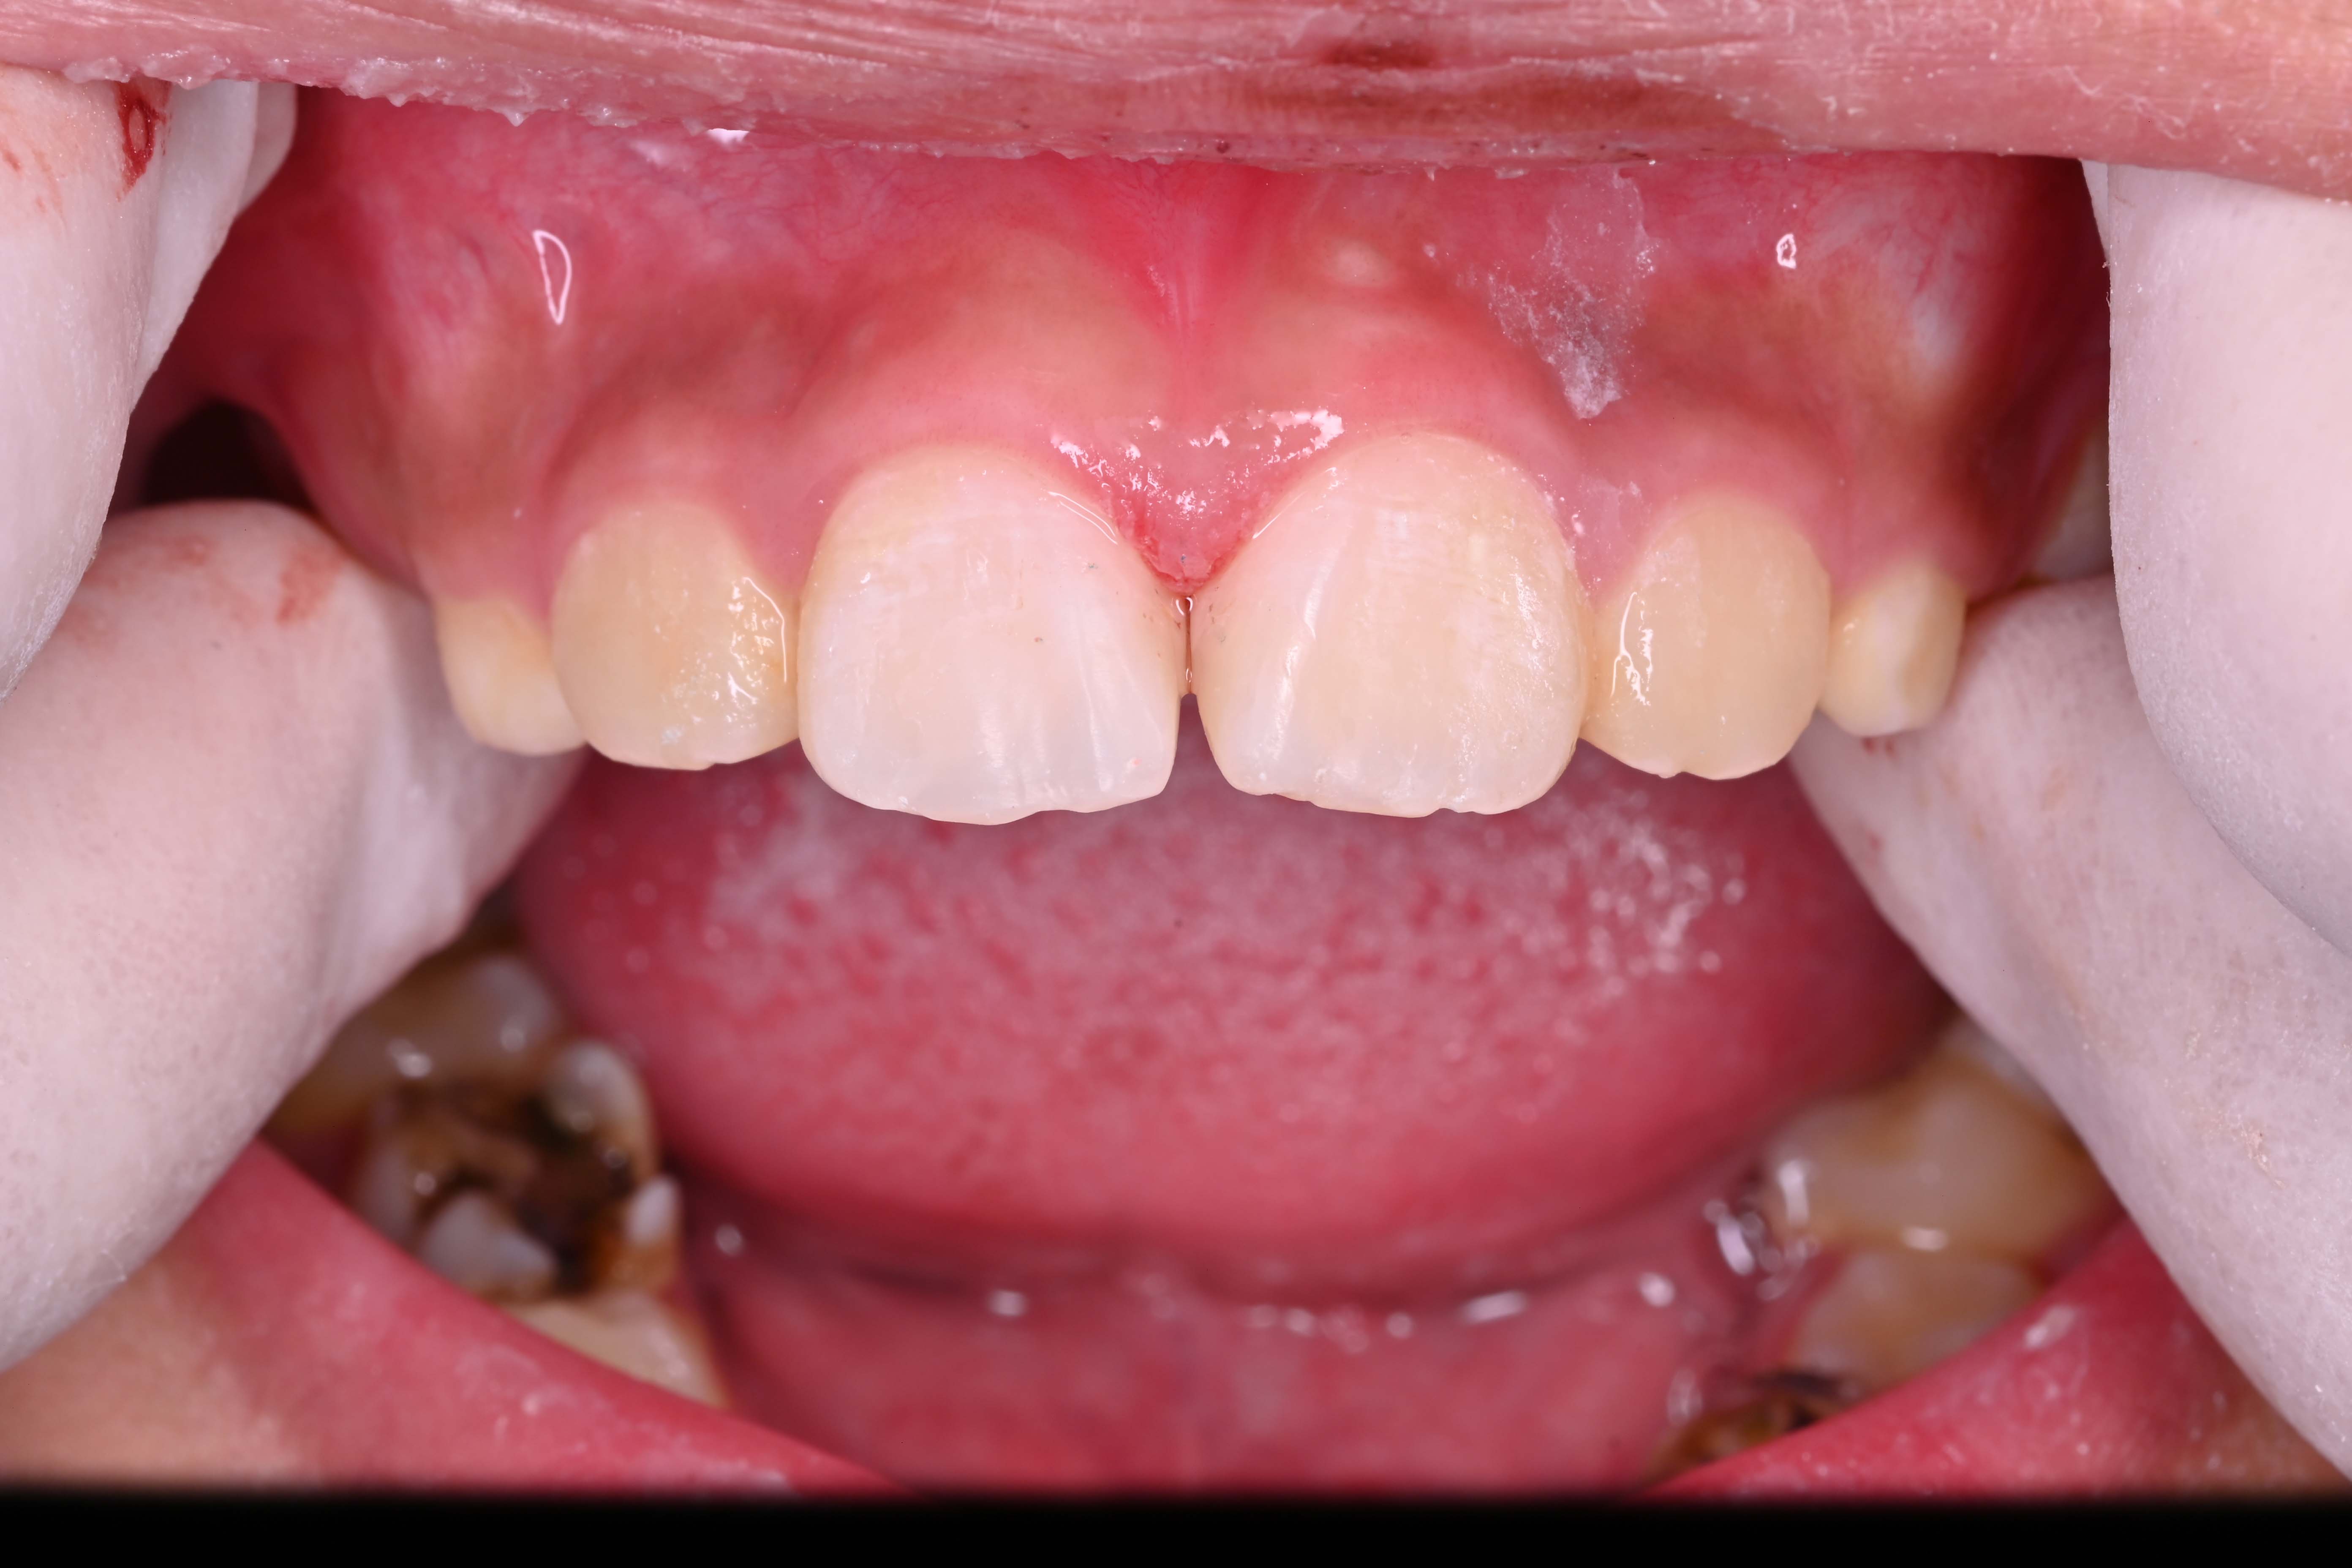

前牙树脂直接修复

前牙树脂关缝

术前 术前

术后 术后